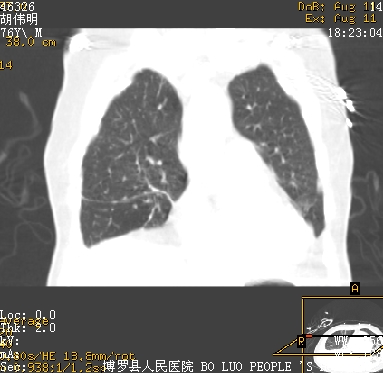

icu病人,几天都没明确诊断。m,76y,咳嗽、咳痰1周,伴气促,右胸痛入院,pe:t38.3c p135 r25 bp135/85。双肺可闻及大量湿罗音,心、腹未见明显异常。诊断:1心衰?2肺部感染?3冠心病?

9号平片

11号ct